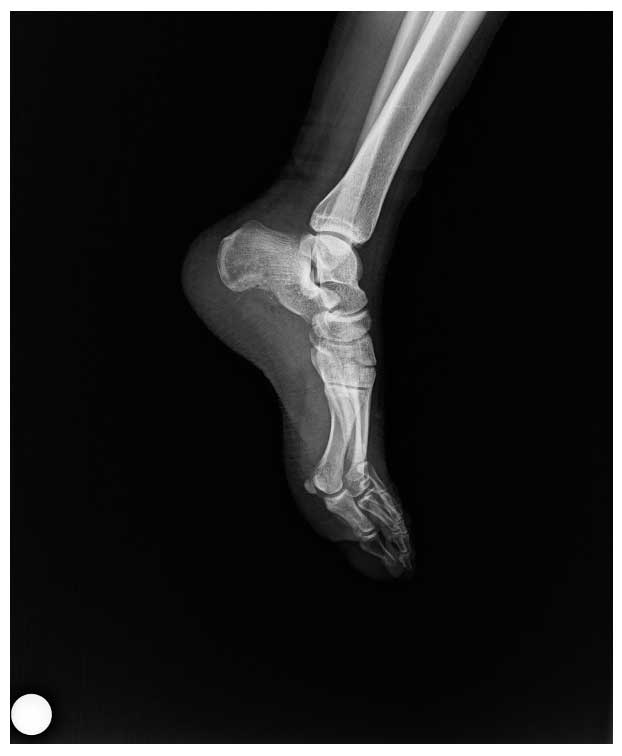

Ameliyat Öncesi: Röntgende Kalkaneus’ta düzensizlik ve harabiyet görülmekte.